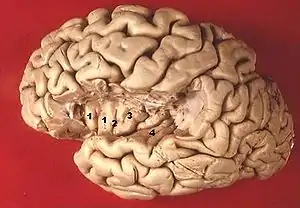

El lóbulo de la Ínsula se encuentra ubicado en la profundidad lateral del cerebro, dentro del surco lateral (cisura de Silvio), que separa las cortezas temporal y parietal inferior. Estas regiones corticales superpuestas se conocen como opércula; parte de los lóbulos frontal, parietal y temporal forman una opércula sobre la ínsula, por ello la ínsula no es visible en la cara externa del cerebro y queda cubierta por las estructuras citadas.

Tiene forma triangular con vértice antero-inferior. Presenta un surco (anatomía) central vertical, que determina un sector anterior con dos pequeños surcos superficiales, delimitando tres cortos giros cerebrales. El sector posterior presenta un giro más largo.[2]